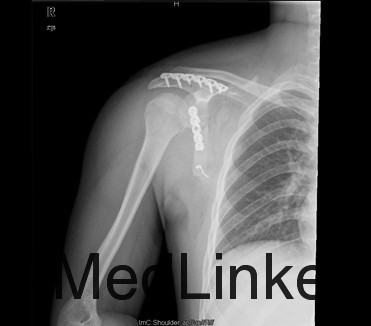

诊断:右肩胛骨粉碎性骨折 治疗:拟行右肩胛骨骨折切开复位内固定术

肩胛体部骨折主要为直接暴力引起,如重物或火器伤直接损伤肩胛骨体部,多为粉碎性骨折,有时亦有横行或斜行骨折,因肩胛骨前后均有肌肉保护,多无明显骨折移位,但须注意有无肋骨骨折或胸腔脏器伤。